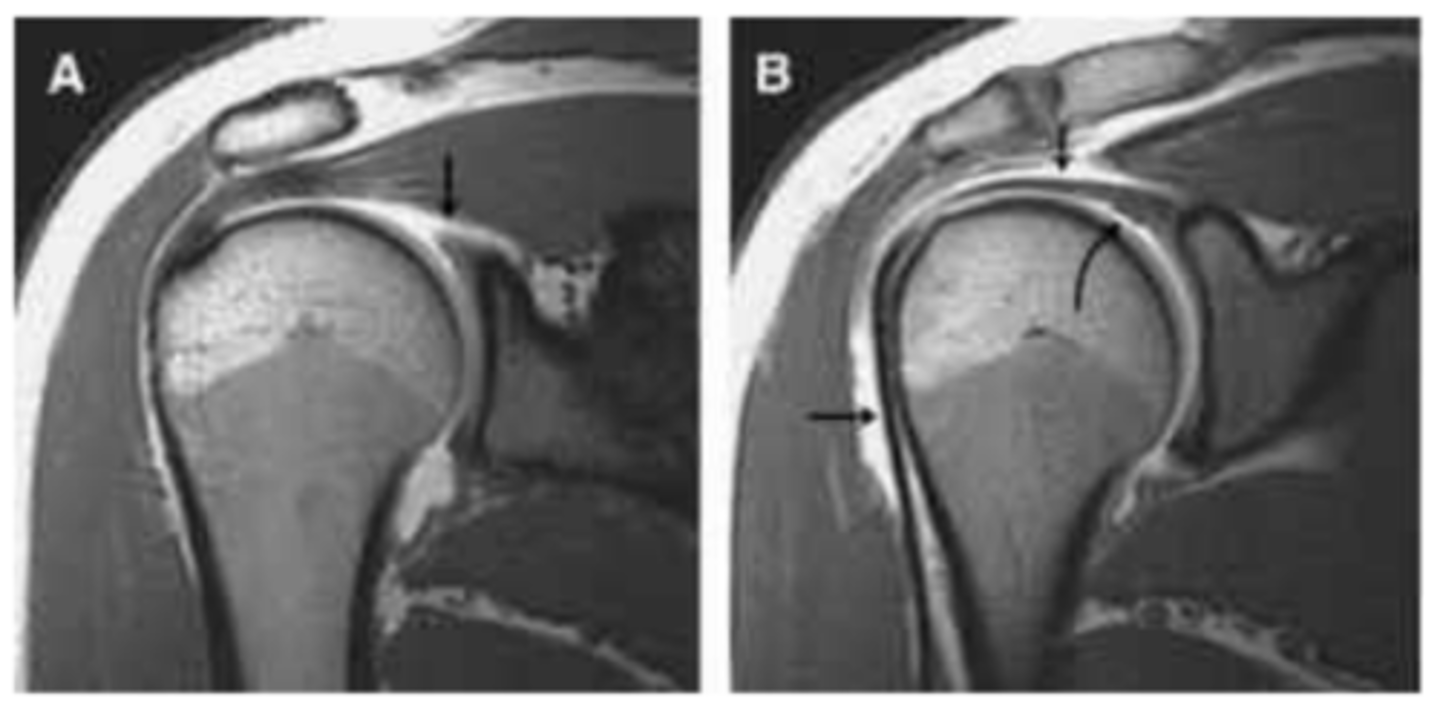

SLAP tear

What does the image show?